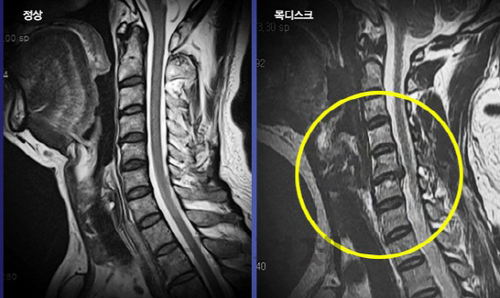

목 디스크는 목의 디스크(경추 디스크)에서 출현하는 질환으로, 경추 디스크 사이의 연골판이 터져 디스크 내부 물질이 경추 신경을 자극해 통증이나 저림증 등의 증상을 유발 해요. 목 디스크는 일상생활에서의 안 좋은 자세나 많은 운동, 부상 등이 이유가 되는 것이 될 수 있기도하고, 시간이 지날수록 발생 확률이 높아져요. 목 디스크의 증상으로는 목 부위의 통증, 팔의 저림, 근육 약화 등이 있으며, 증상이 난폭한 경우 수술 등의 치료가 필요할 수 있어요. 그리하나 대개의 경우 치료 없이도 시간이 지나면 증상이 호전되는 경우가 대부분입니다.